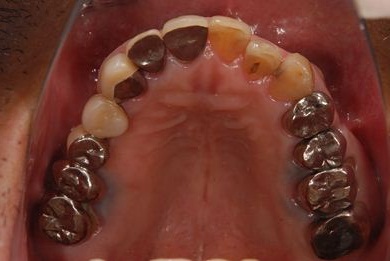

インプラントの症例写真 IMPLANT

インプラント治療

| 性別/年齢 | 男性 / 53歳 | ||||||||||||||||||||||||||||||||

| 主訴 | 左下奥歯2本のインプラント治療を希望。 | ||||||||||||||||||||||||||||||||

| 治療方針 | 左下欠損部分をインプラント治療にて機能的・審美的回復を行う。 | ||||||||||||||||||||||||||||||||

| 治療内容 | インプラント2本、ハイブリッドセラミッククラウン2本 | ||||||||||||||||||||||||||||||||

| 総治療費 | 399,000円 | ||||||||||||||||||||||||||||||||

| 治療期間 | 9ヶ月 |